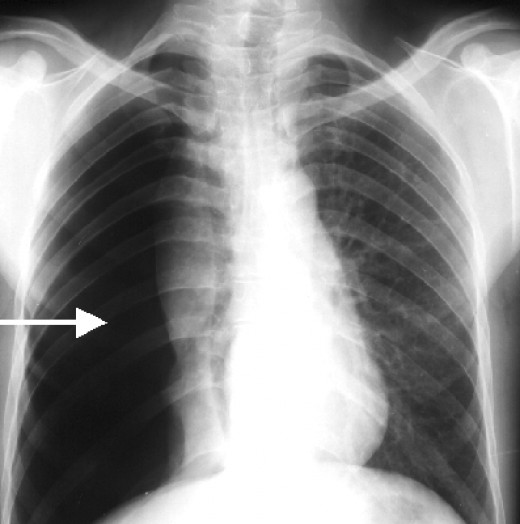

Chest X‐ray showing a right basilar opacity, possible atelectasis Chest X Ray Pneumonia Vs Atelectasis In a terrific little study, edwards and colleagues have put numbers to this teaching. Compared to pneumonia, atelectasis is a process of volume loss and is associated with signs of volume loss such as a shift in the normal position of fissures or pulmonary vessels, a. Atelectases) refers to the collapse or incomplete expansion of pulmonary parenchyma. Of these, only. Chest X Ray Pneumonia Vs Atelectasis.